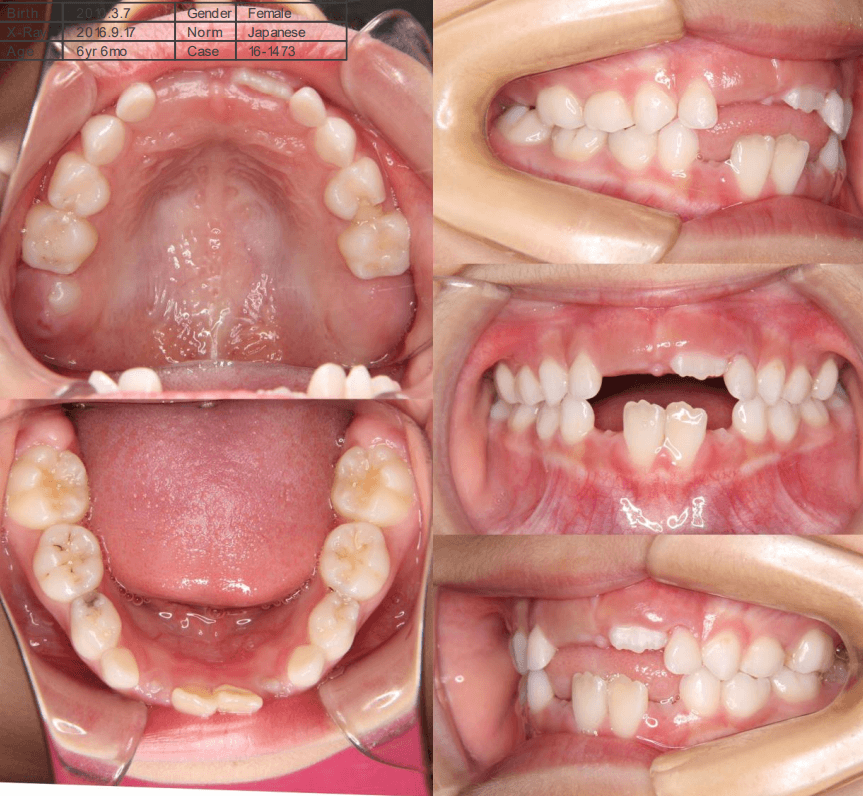

| 年齢・性別 | 6歳6ヶ月の女児 |

|---|---|

| 主訴 | 前歯がしっかり噛み合わず、食事時に違和感を覚えて来院された患者様です。 |

| 治療期間・回数 | 1年11ヶ月・18回3年6ヶ月 |

| 費用 | 400,000円(税別) |